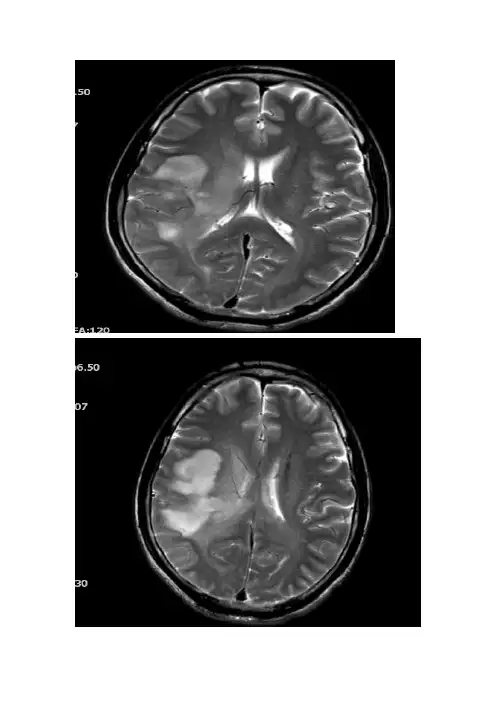

T2WIT1WIT2WI---FLAIRDWIADCT2WI---冠状位SWIT1WI----增强DTT头颅MRI(平扫+增强):右侧大脑半球内见大片状异常信号影,T1WI呈低信号,T2WI及水抑制像呈高信号,DWI呈高信号,边缘欠清,有轻度占位效应,右侧脑室呈轻度受压改变,增强后扫描呈轻度不均匀强化,最大层面强化范围约5.6X2.4cm,周边水肿影未见明显强化,中线结构尚居中,双侧筛窦内见粘膜增厚影,窦壁骨质未见明显破坏。

MR灌注成像示:内源性灌注示病灶区较对照组明显灌注稍增高。

病灶区MRS:代谢物波谱图主要显示NAA、Cr、Cho峰,病灶区NAA峰明显下降,Cho峰明显升高。

头颅DTT:右侧大脑半球区皮质纤维束较对侧部分中断、稀少。

头颅MRI(平扫+增强+MRS+DTI+灌注):1、右侧颞顶叶占位,考虑胶质瘤可能性大。

2、双侧筛窦炎症。